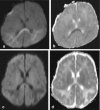

Background and purpose: The splenium of the corpus callosum is the most posterior part of the corpus callosum. Its embryological development, anatomy, vascularization, function, imaging of pathology, possible pathophysiological mechanisms by which pathology may develop and the clinical consequences are discussed.

Methods: A literature-based description is provided on development, anatomy and function. MR and CT images are used to demonstrate pathology. The majority of pathology, known to affect the splenium, and the clinical effects are described in three subsections: (A) limited to the splenium, with elaboration on pathophysiology of reversible splenial lesions, (B) pathology in the cerebral white matter extending into or deriving from the splenium, with special emphasis on tumors, and (C) splenial involvement in generalized conditions affecting the entire brain, with a hypothesis for pathophysiological mechanisms for the different diseases.

Results: The development of the splenium is preceded by the formation of the hippocampal commissure. It is bordered by the falx and the tentorium and is perfused by the anterior and posterior circulation. It contains different caliber axonal fibers and the most compact area of callosal glial cells. These findings may explain the affinity of specific forms of pathology for this region. The fibers interconnect the temporal and occipital regions of both hemispheres reciprocally and are important in language, visuospatial information transfer and behavior. Acquired pathology may lead to changes in consciousness.